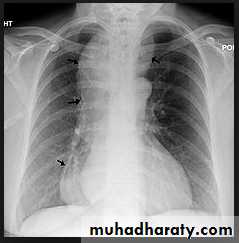

Marked lymphadenopathy (dotted lines) is seen in the region of both hila in the right paratracheal region (A).The transverse contrast-enhanced computed tomography scan of the upper chest (B) clearly shows the ascending and descending aorta (Ao) as well as the pulmonary artery (PA) and superior vena cava. The right and left main-stem bronchus area also is seen. Arrows, the extensive lymphadenopathy.

Hodgkin Lymphoma. A. Posteroanterior chest radiograph in a 35-year-old man shows a large, lobulated mediastinal mass. B. Contrast-enhanced CT at the level of the aortic arch shows bulky anterior and middle mediastinal lymphadenopathy